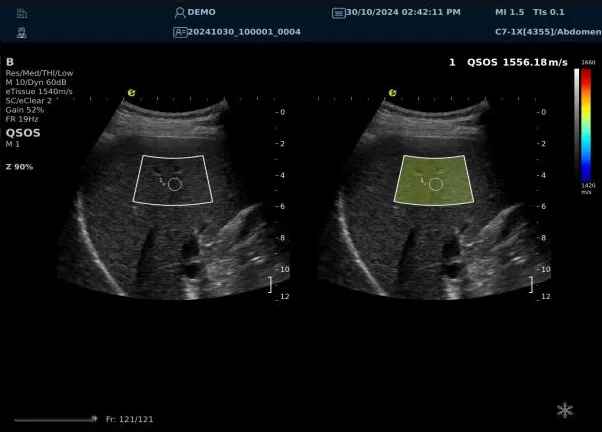

640.jpg123 (2).jpg可以设想,单位时间可发射的脉冲波越多、单位面积可发射的脉冲波越密集,得到的数据结果就越快、越多。也就是说,如果医生希望得到实时、大幅的声速定量图像,就需要超声系统具备“超快速”发射和接收的能力,百乐博平台医疗(ESI)ePascal东风系列超声平台的200+倍成像速度,成为了这项新技术得以临床应用的重要条件。

以上为应用声速定量成像技术检查肝脏的超声图像,图中在取样框内选择了三个测量区域,得出了各区域内的组织声速值以及声速衰减系数等结果。